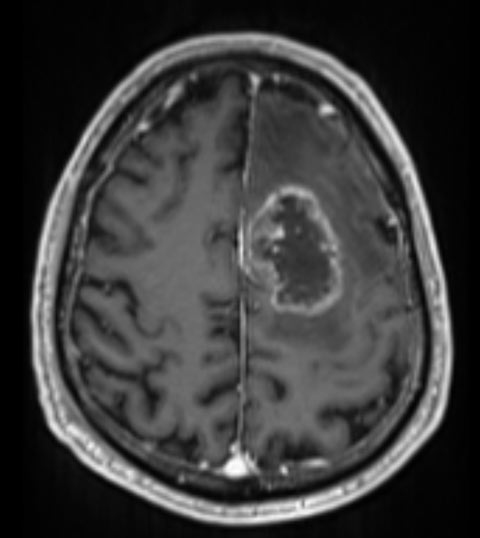

בן 65 עם גליומה מדרגה גבוהה באונה פרונטלית משמאל אשר נותח בעירות לכריתה.